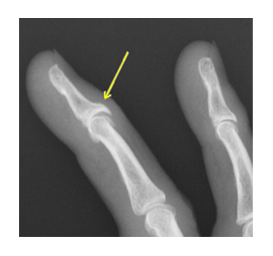

ヘバーデン結節は指の第1関節変形し曲がってしまう原因不明の疾患です。

ヘバーデン結節